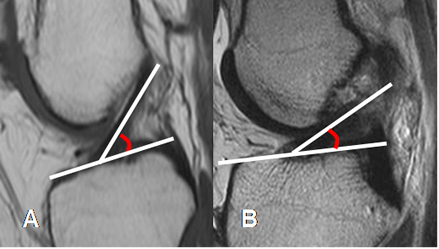

Fig 16. LCA normal.

A: RM sagital en T1. Angulo normal de vértice superior, con la línea intercondilea.

B: RM sagital en T2. Ruptura del LCA, con ángulo de vértice inferior.